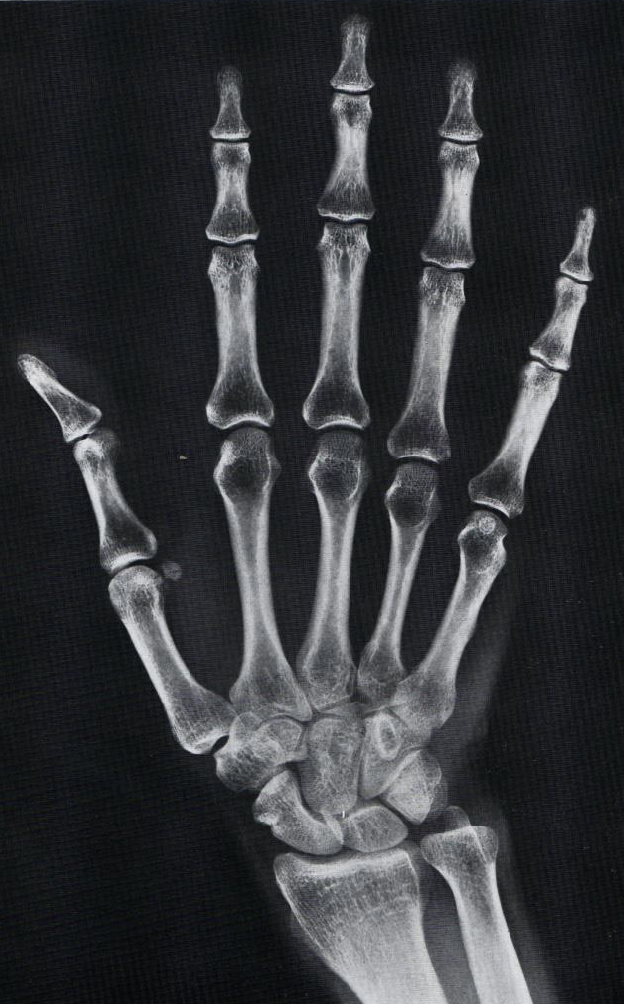

What is this view of the hand? What views are missing?

PA

MISSING:

Lateral

Lateral Oblique (PA)

Medial Oblique (PA)

Scaphoid